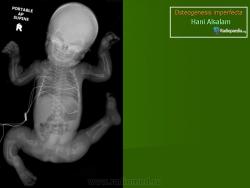

Клиническая картина зависит от типа заболевания, возраста его проявления и от тяжести поражения скелета и других органов. Если болезнь выявлена у новорожденного, то это, скорее всего, несовершенный остеогенез типа II (традиционное название - врожденный несовершенный остеогенез). Прогноз в этом случае крайне неблагоприятный. При несовершенном остеогенезе типа II ребенок рождается со множественными переломами длинных трубчатых костей; после заживления переломов кости укорачиваются, утолщаются и деформируются. Рождение мертвого плода или ранняя смерть новорожденного обычно вызваны дыхательной недостаточностью или повреждением ЦНС. При несовершенном остеогенезе типа III переломы отмечаются реже; нет врожденного укорочения и деформаций конечностей. Такие дети обычно живут несколько лет, причем деформации длинных костей прогрессируют). И в этом случае непосредственной причиной смерти обычно бывает дыхательная недостаточность. Несовершенный остеогенез типов I и IV протекает не так тяжело. Больные доживают до пожилого возраста. Повышенная ломкость костей сопровождается слабостью и разболтанностью суставов, кровоподтеками и кондуктивной тугоухостью (обусловленной плохой костной проводимостью). Для подтипов IB и IVB характерна дисплазия зубов, а именно нарушение развития эмали и дентина (dentinogenesis imperfecta). Зубы имеют янтарный, желто-коричневый или голубоватый цвет из-за нарушения образования дентина. Постоянные зубы нередко колоколообразные, суженные у шейки. Отличительная черта несовершенного остеогенеза типа I - устойчивая голубая окраска склер. Несовершенный остеогенез типа IV по клинической картине сходен с несовершенным остеогенезом типа I, но у детей младшего возраста склеры имеют нормальный белый цвет. При оценке окраски склер надо помнить, что голубые склеры могут быть и у здоровых новорожденных и грудных детей.

Тип 2 [OMIM 166210 перинатально летальная форма R или p (OMIM 259400)]. В основном формируется грубоволокнистая кость; тяжёлая летальная форма, дети рождаются мёртвыми или умирают в неонатальном периоде, имеют пониженную массу тела, короткие искривлённые конечности и множественные переломы